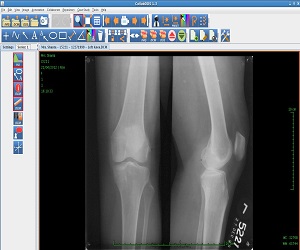

CollabDDS provides a real time collaborative environment to visualize medical (Skeletal) and dental images (digitized X-Ray images or DICOM data) for diagnosis and treatment planning. CollabDDS has various image processing tools to visualize the data and also annotate. An inbuilt repository of annotated images can be used for education. Further it enables real time collaboration for diagnosis between physician at PHC level and experts at medical colleges and hospitals. CollabDDS is unique as it allows the viewing and processing of digitized X-Rays in various standard image formats like JPEG and DICOM and also allows this data to be saved for later review/ study.

The patient submits his/her X-Ray to the Primary Health Center or Secondary Health Center. This is transmitted to the connected higher level centers after scanning it. The digitizer at the time of scanning permits the technician to enter certain details and have the X-Ray in DICOM format if required. DICOM files along with the relevant diagnosis are stored in the Repository at the data center to be accessible for any future reference and teaching purposes.